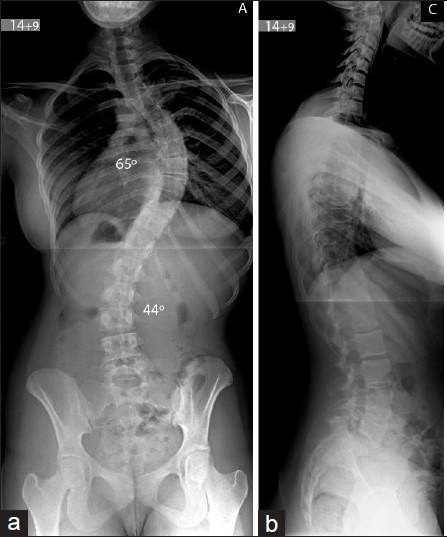

Обзорный рентген позвоночника. Фото из открытых источников

Диагноз "сколиоз" не ставится на глаз, только обзорный рентген позвоночника в двух проекциях может подтвердить его наличие!